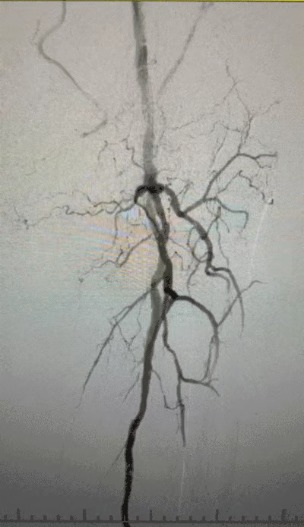

Los hallazgos clínicos

· Examen físico: Pulsos femorales débiles; ausencia de pulsos poplíteo y dorsalis pedis; ulceración en el primer dedo del pie izquierdo; necrosis en el primer y segundo dedo del pie derecho

· Imagen preoperatoria: estenosis calcificada difusa y grave en arterias bilaterales de las extremidades inferiores

Enfoque de tratamiento

Dada la condición vascular compleja, seleccionamos el sistema de catéter de dilatación con balón periférico IVL de ThorCrack. Debido a la tolerancia limitada del paciente, se realizaron procedimientos de intervención por etapas en ambas extremidades inferiores.

Resultado quirúrgico

Después del procedimiento, la estenosis arterial mejoró significativamente, el flujo sanguíneo aumentó y la temperatura de la piel aumentó. No hubo complicaciones postoperatorias. Tanto el paciente como el equipo quirúrgico estaban muy satisfechos con los resultados.